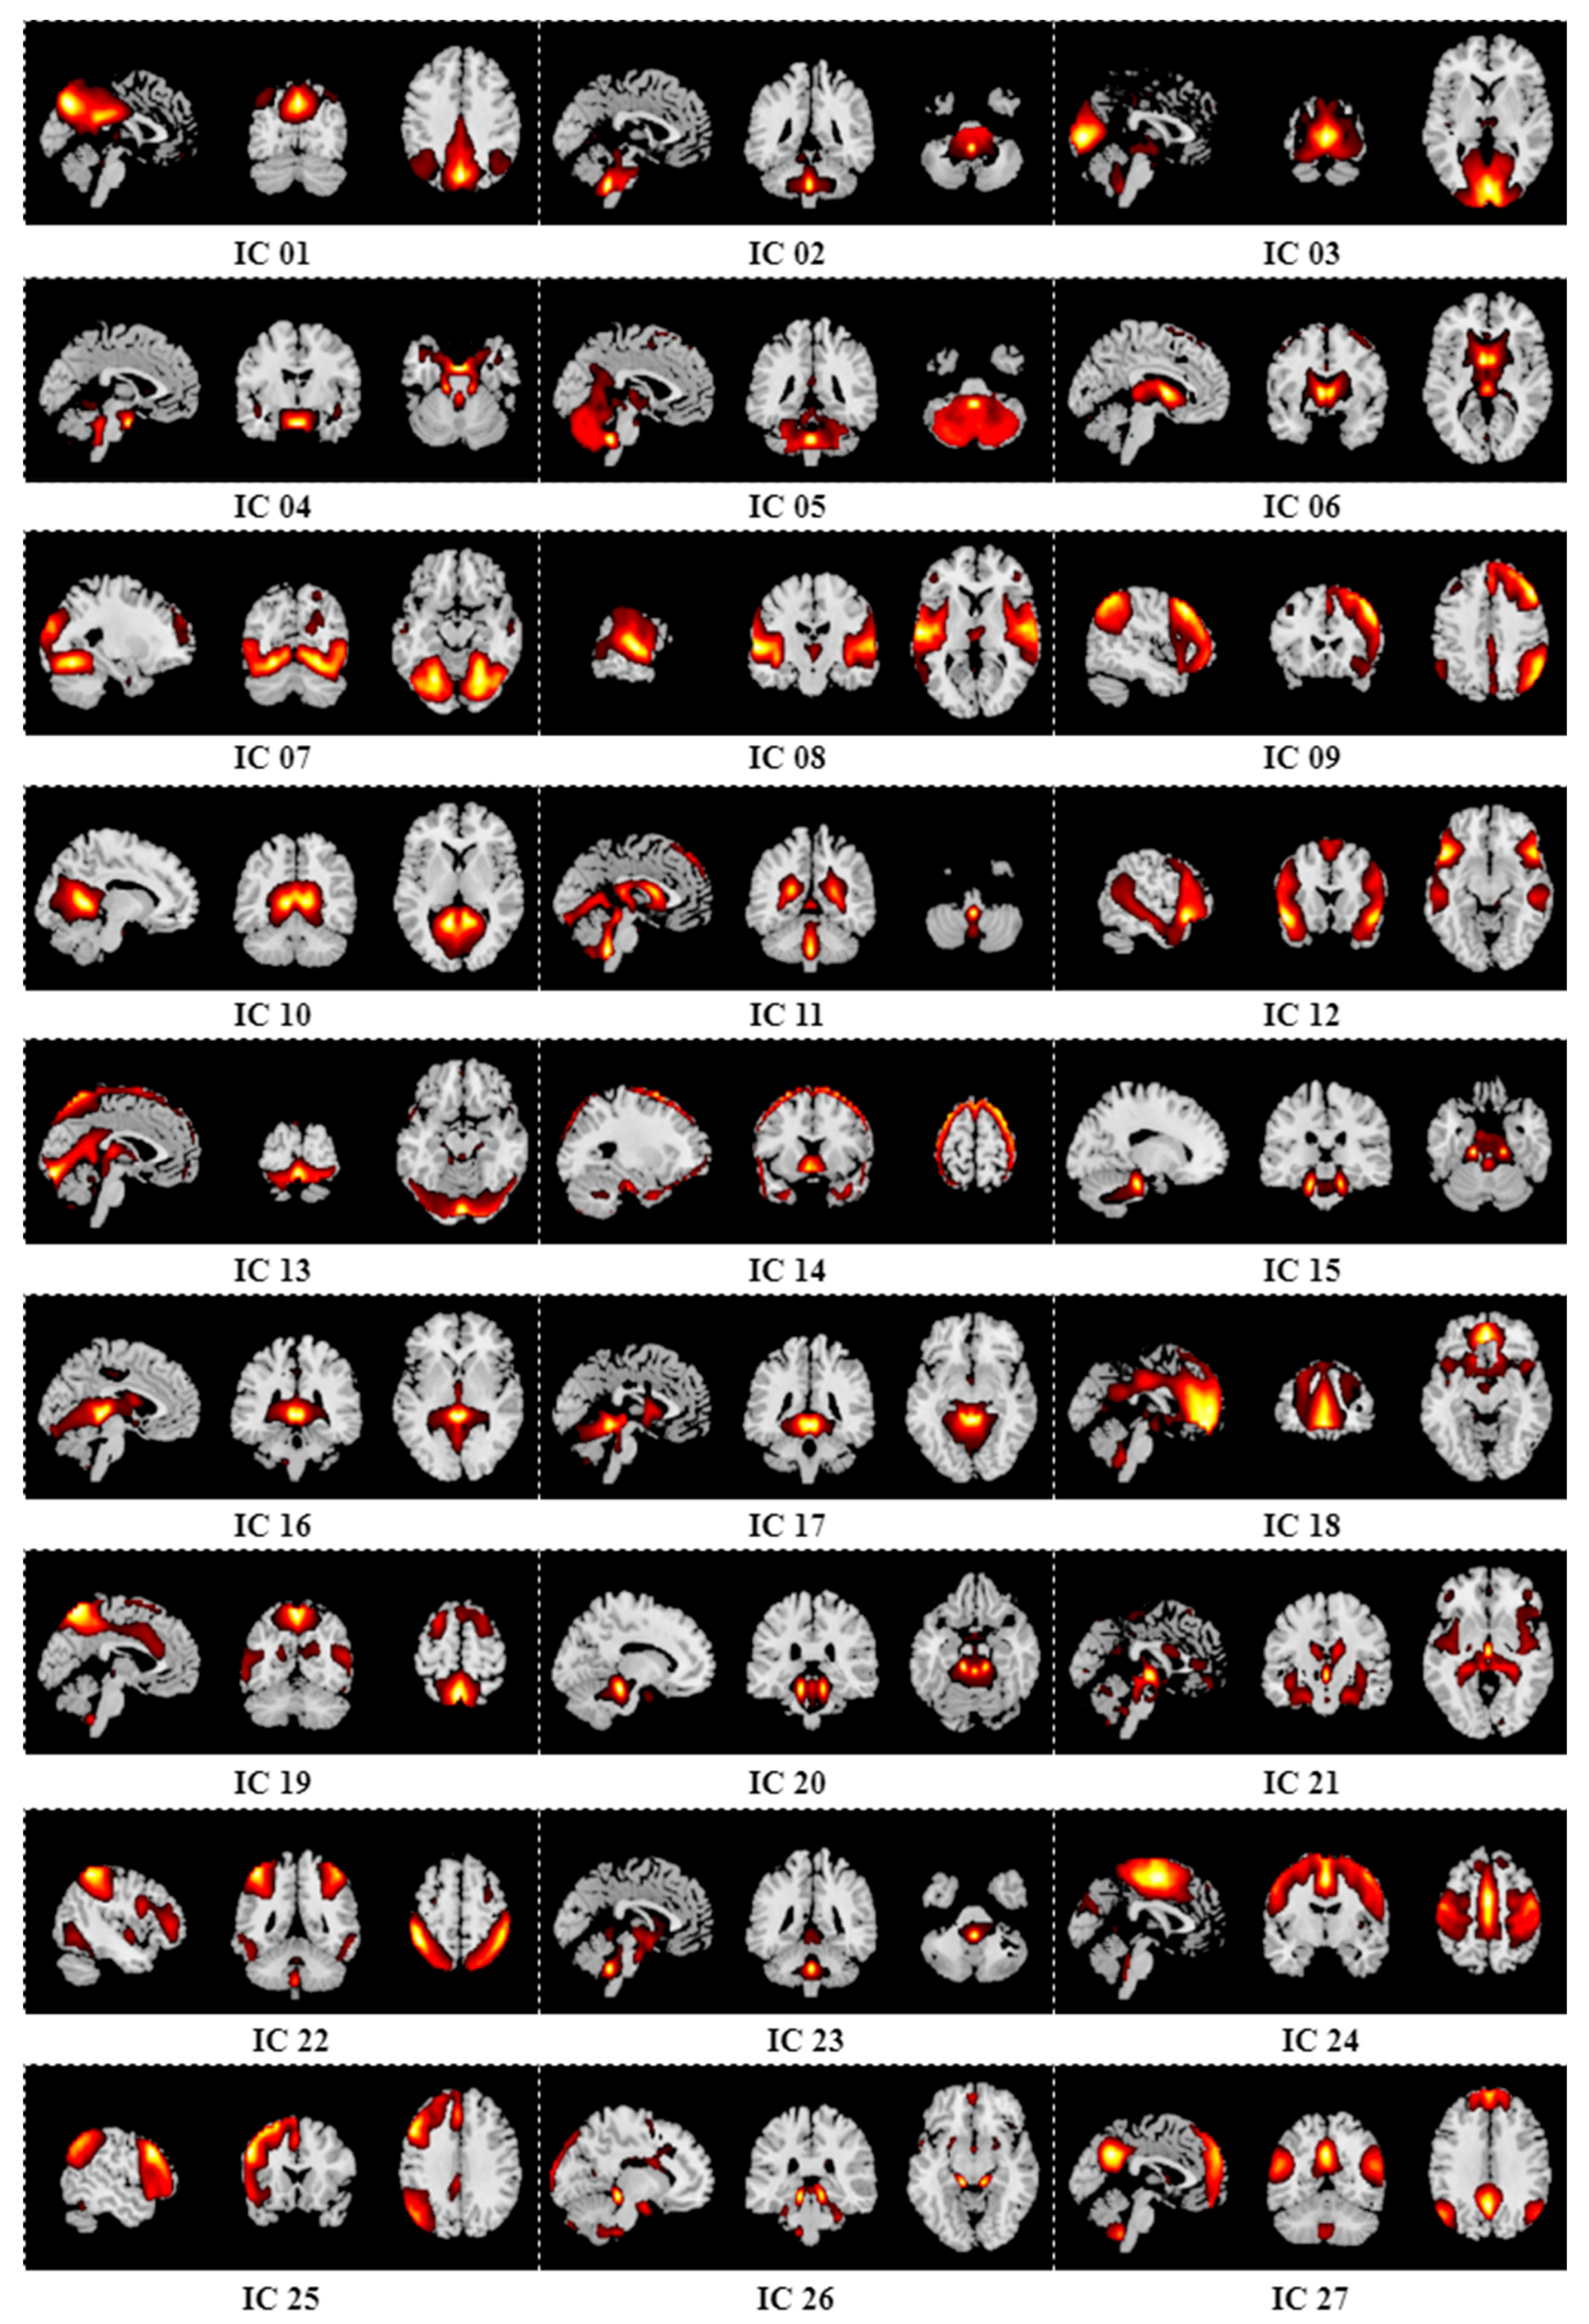

Appendix B. Results of Group ICA

| 27 | 69.52% | 81.15% | 73.71% | 66.61% |